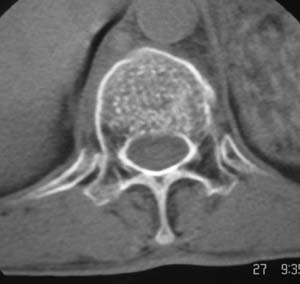

以下是引用余辉在2008-4-27 17:12:00的发言:[br]骨质疏松伴病理性压缩性骨折,椎骨骨松质密度减低,椎体骨小梁稀疏且普遍呈火柴头样改变,椎体无膨胀,无软组织肿块

以下是引用mzh123在2008-4-27 19:33:00的发言:[br]除压缩骨折表现外 还有许莫氏结节改变

以下是引用随光逐影在2008-4-27 21:29:00的发言:[br]除压缩性骨折外,还有许莫氏结节及骨质疏松表现。